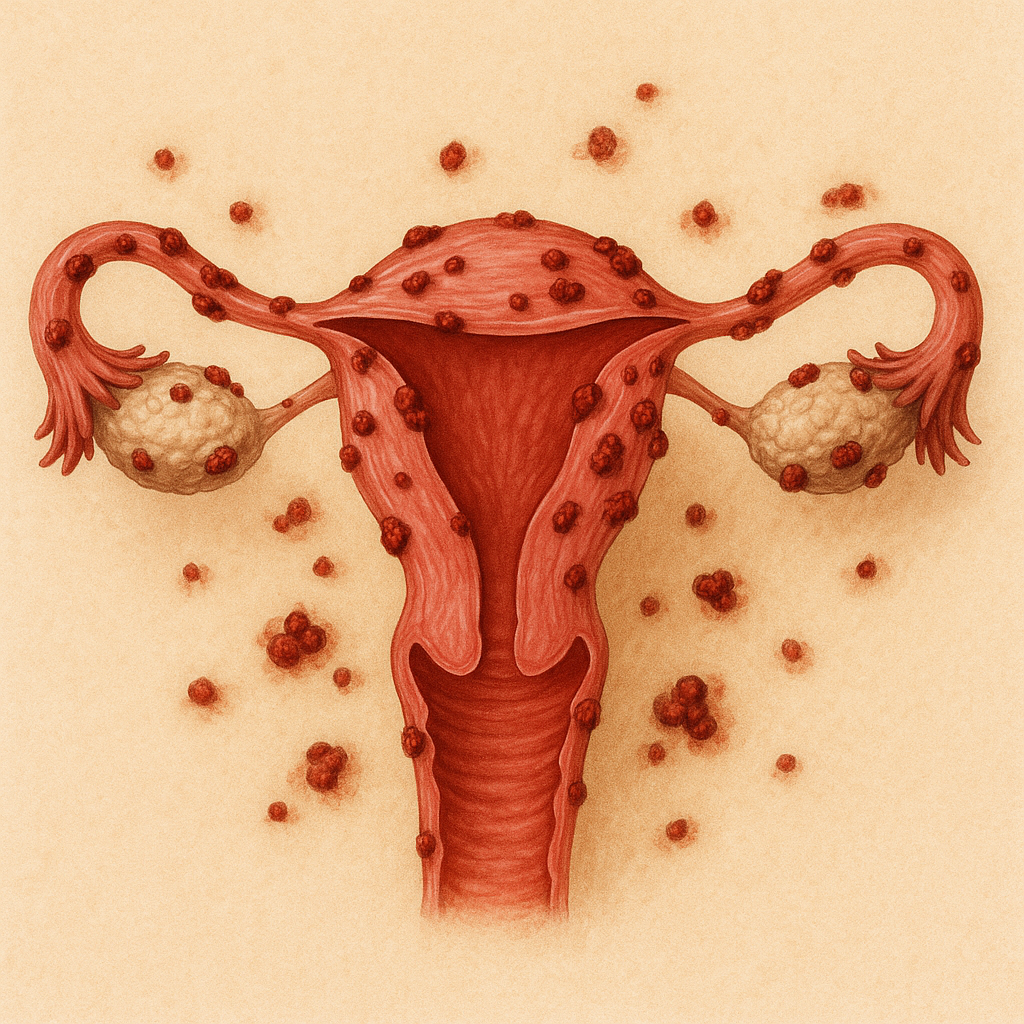

# Female